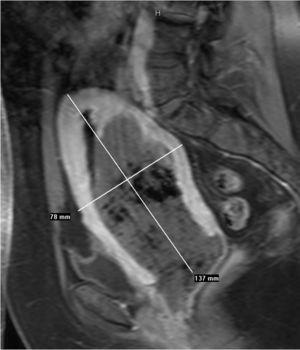

Se realiza RM pélvica (fig. 2B), en la que se visualiza una masa amorfa rodeada de líquido en la cavidad endometrial. A las 24 h, la paciente acude al servicio de urgencias por la expulsión espontánea de un mioma de 7 cm de diámetro con un pedículo muy fino, que se extrajo con facilidad. El resultado anatomopatológico es de mioma necrosado, en el seno del cual aparece material translúcido que corresponde al material de embolización Embosphères® (Biosphère Medical France) (fig. 3).

Figura 2B. Resonancia magnética pélvica (secuencia T1 con contraste sagital). Estudio postembolización. Ocupación por masa amorfa en el interior de la cavidad endometrial con apertura del cuello uterino.